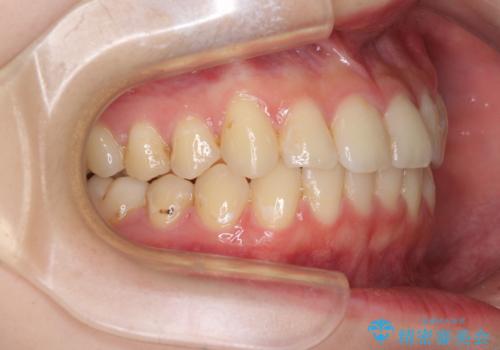

- 上下前歯のデコボコを気にして来院された患者様です。

以前矯正をした後戻りということで、歯列不正はそれほど大きくなかったため、インビザライン・ライトを用いて矯正治療を行うこととしました。

前歯のデコボコが残っており、シミュレーション通りに動いていない部分がありましたが、再矯正であることやご本人の満足いくところまでデコボコが改善されたとのことで、治療を終了することとしました。